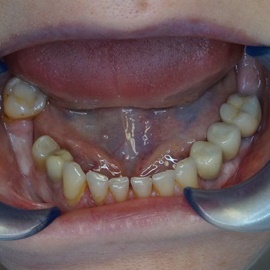

Brakujących pięć zębów dolnych w odcinku wargowym. Rekonstrukcja tkanek i rehabilitacja protetyczna.